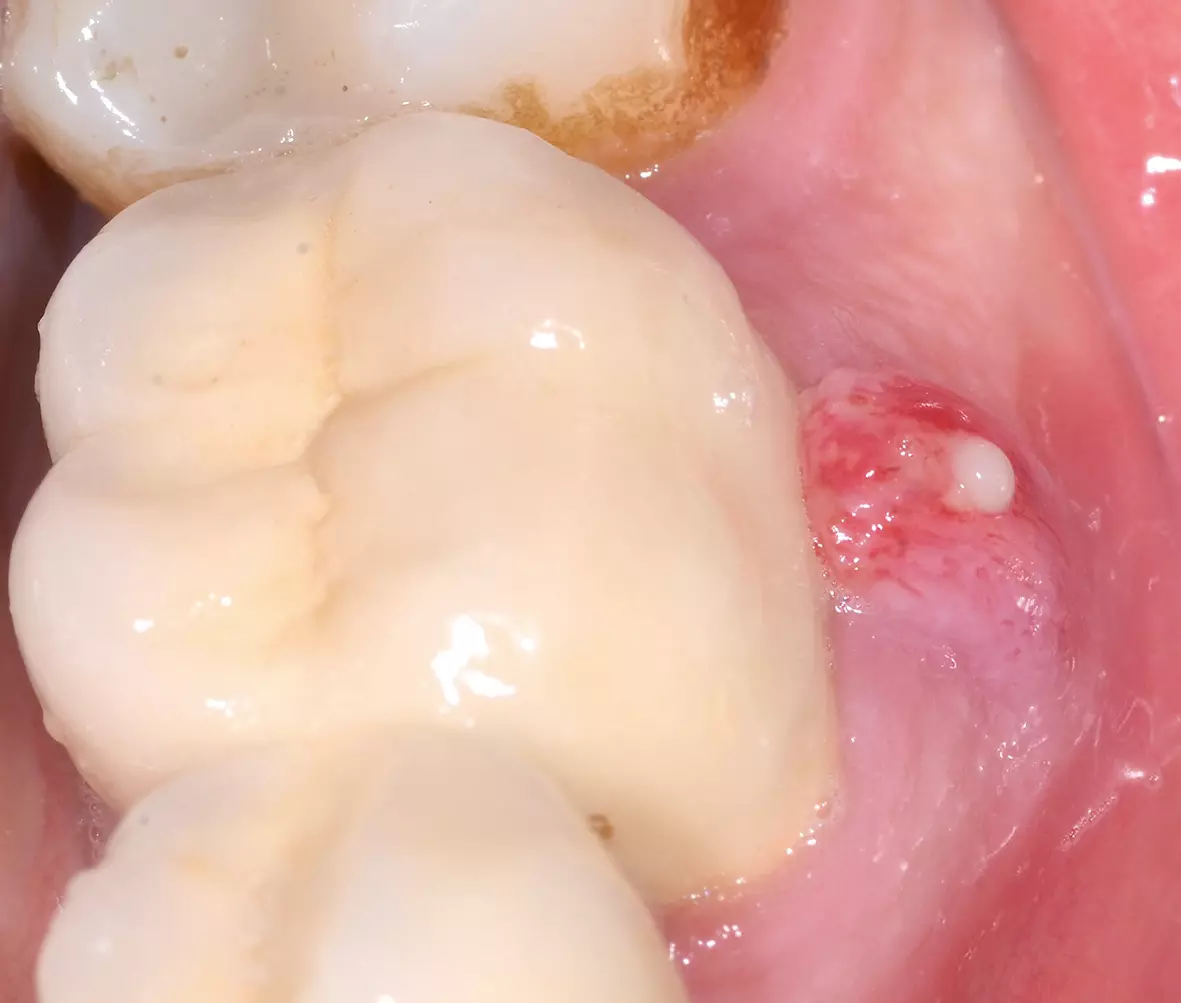

Freilegung nach 3 Monaten

Nach 3 Monaten Einheilzeit wurden die Implantate freigelegt und mit Gingivaformern (jeweils 4,1 x 5 mm) versorgt. Die Abbildung 13 zeigt den Zustand zehn Tage nach Freilegungsoperation und Entfernung der Gingivaformer. Die prothetische Versorgung (Abb. 14 und 15) stellte unser praxiseigenes Labor her. Die Patientin stellt sich regelmäßig zur Kontrolle und Zahnreinigung in unserer Praxis vor. Drei Jahre nach abschließender prothetischer Versorgung zeigen sich die Implantate klinisch und radiologisch gut osseointegriert (Abb. 16).